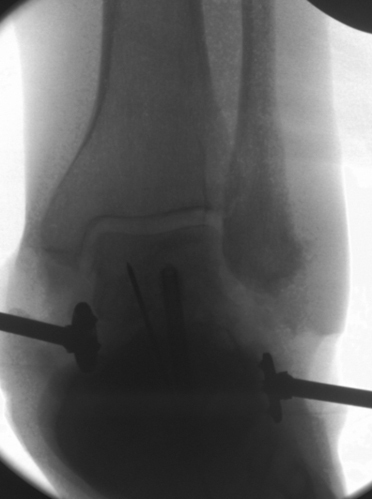

TOTAL ANKLE REPLACEMENT :: ORIF CALCANEUS :: ORIF ANKLE FRACTURE DISLOCATION :: COMPLEX BUNION AND LESSER TOE CORRECTION :: TALUS FRACTURE -1 :: TALUS FRACTURE -2 :: LISFRANC REPAIR :: COMPLEX TRIPLE ARTHRODESIS 1 :: COMPLEX TRIPLE ARTHRODESIS 2 :: MINIMALLY INVASIVE BUNION REPAIR 1 :: MINIMALLY INVASIVE BUNION REPAIR 2 :: ARTHROSCOPIC CARTILAGE REPAIR :: TENEX SPUR DEBRIDEMENT :: Haglunds Debridement and Achilles Repair